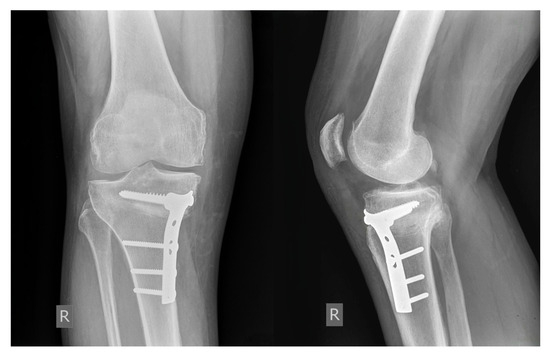

The Magnitude of Varus Correction and Its Influence on Postoperative Patellar Height and Posterior Tibial Slope in Medial Open-Wedge High Tibial Osteotomy

by Veljko Santic, Nikola Matejcic, Marta Santic and Nikola Grzalja

J. Clin. Med. 2026, 15(4), 1469; https://doi.org/10.3390/jcm15041469 - 13 Feb 2026

Objectives: Medial open-wedge high tibial osteotomy (MOWHTO) is a surgical procedure used to treat medial compartment osteoarthritis of the knee with varus deformity. The aim of this study was to examine whether a larger correction angle in medial open wedge high tibial [...] Read more.

Objectives: Medial open-wedge high tibial osteotomy (MOWHTO) is a surgical procedure used to treat medial compartment osteoarthritis of the knee with varus deformity. The aim of this study was to examine whether a larger correction angle in medial open wedge high tibial osteotomy (MOWHTO) leads to greater changes in postoperative patellar height (PH) and posterior tibial slope (PTS). Methods: Data from 83 patients who underwent MOWHTO were retrospectively analyzed. Lower limb alignment was evaluated using the hip–knee–ankle angle (HKAA). The PH was assessed using the Insall–Salvati index (ISI), the Blackburne–Peel index (BPI), the Caton–Deschamps index (CDI), the modified Miura–Kawamura index (MKI), and the plateau–patella angle (PPA). The PTS was determined using the Moore–Harvey method. Results: The median correction of HKAA was 8°. A decrease in PH was observed in the majority of cases across all methods, with the highest frequency of postoperative patella infera detected using the MKI. PTS most frequently increased, with a median increase of 3°. A significant association between the magnitude of HKAA correction and patellar height in the overall cohort was observed only for the MKI, whereas in patients with an HKAA correction ≥ 10°, significant associations were found for both the MKI and CDI. No significant association was found between the magnitude of HKAA correction and changes in posterior tibial slope in the overall cohort, while a significant negative correlation was observed in patients with an HKAA correction ≥ 10°. Conclusions: Assessment using the MKI demonstrated greater sensitivity in detecting postoperative PH decrease, particularly in identifying patella infera. The magnitude of HKAA correction was significantly associated with greater changes in PTS and PH in patients with a coronal plane correction of ≥10°. Full article

(This article belongs to the Section Orthopedics)

Show Figures

Figure 1